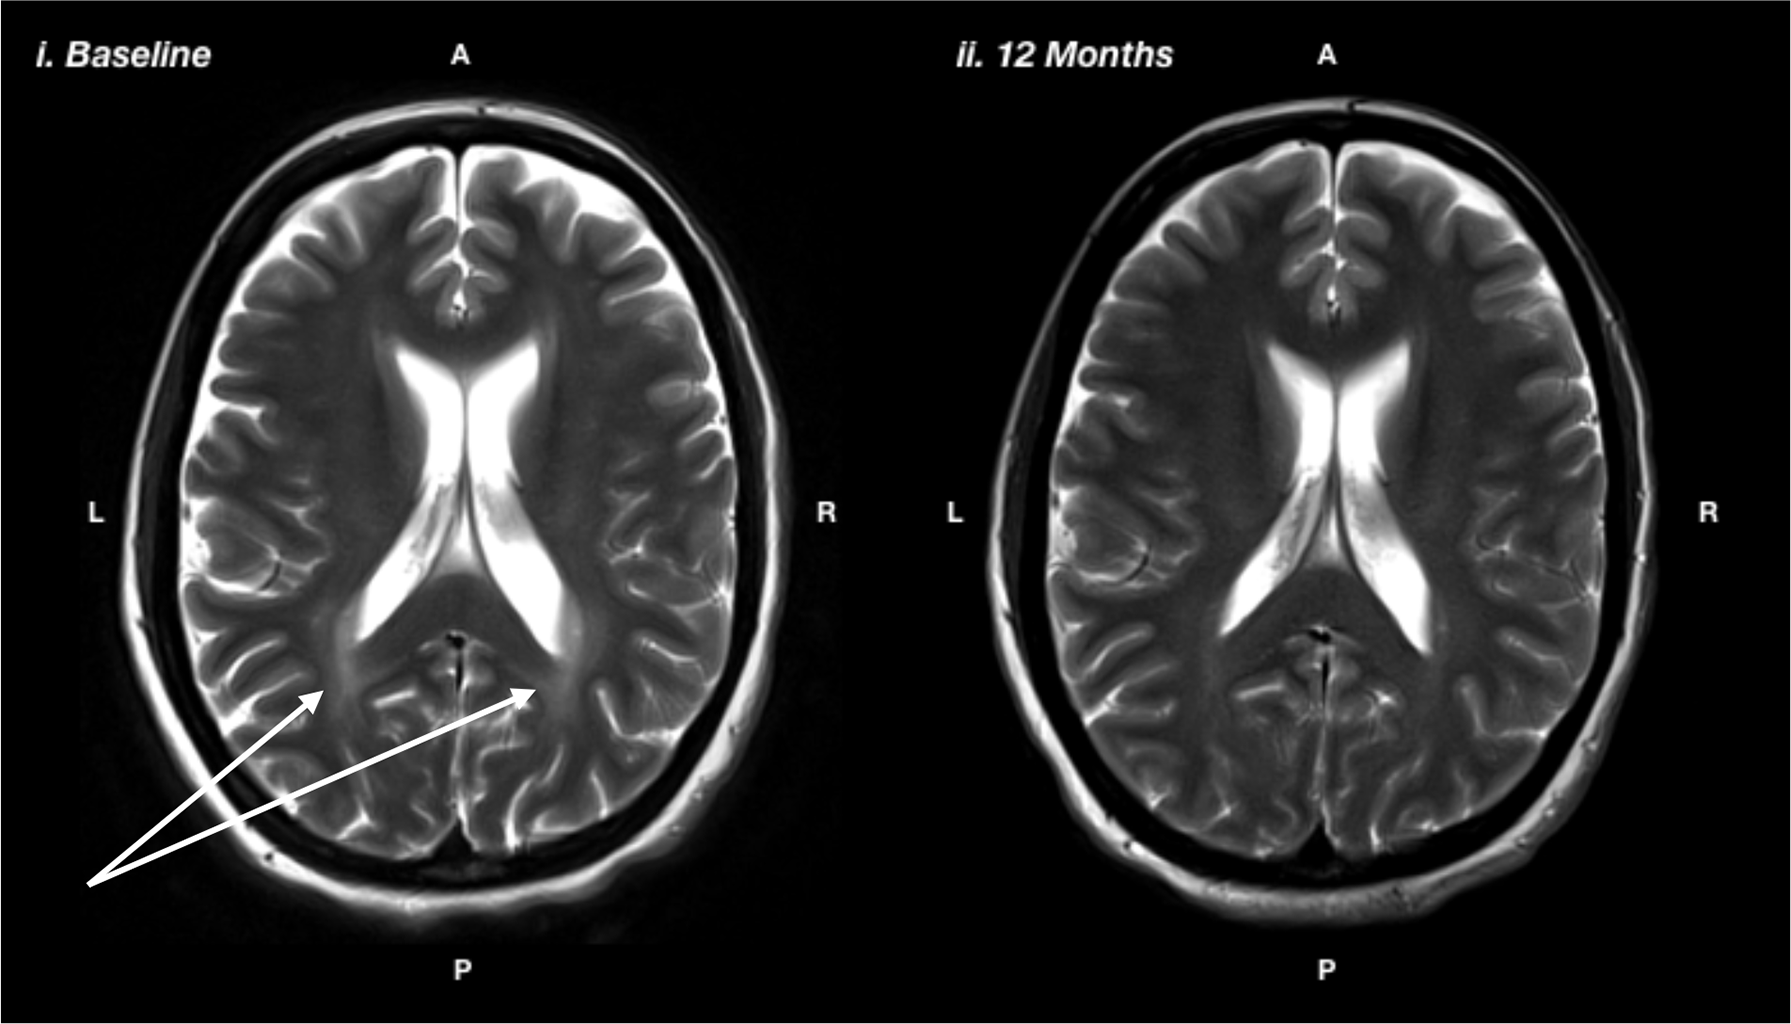

Figure 3

T2-weighted magnetic resonance imaging showing i) baseline: prior to the recommencing diet, and ii) 12 months after recommencing diet, showing reduction in white matter hyperintensity, particularly in the posterior regions, as indicated by the white arrows.